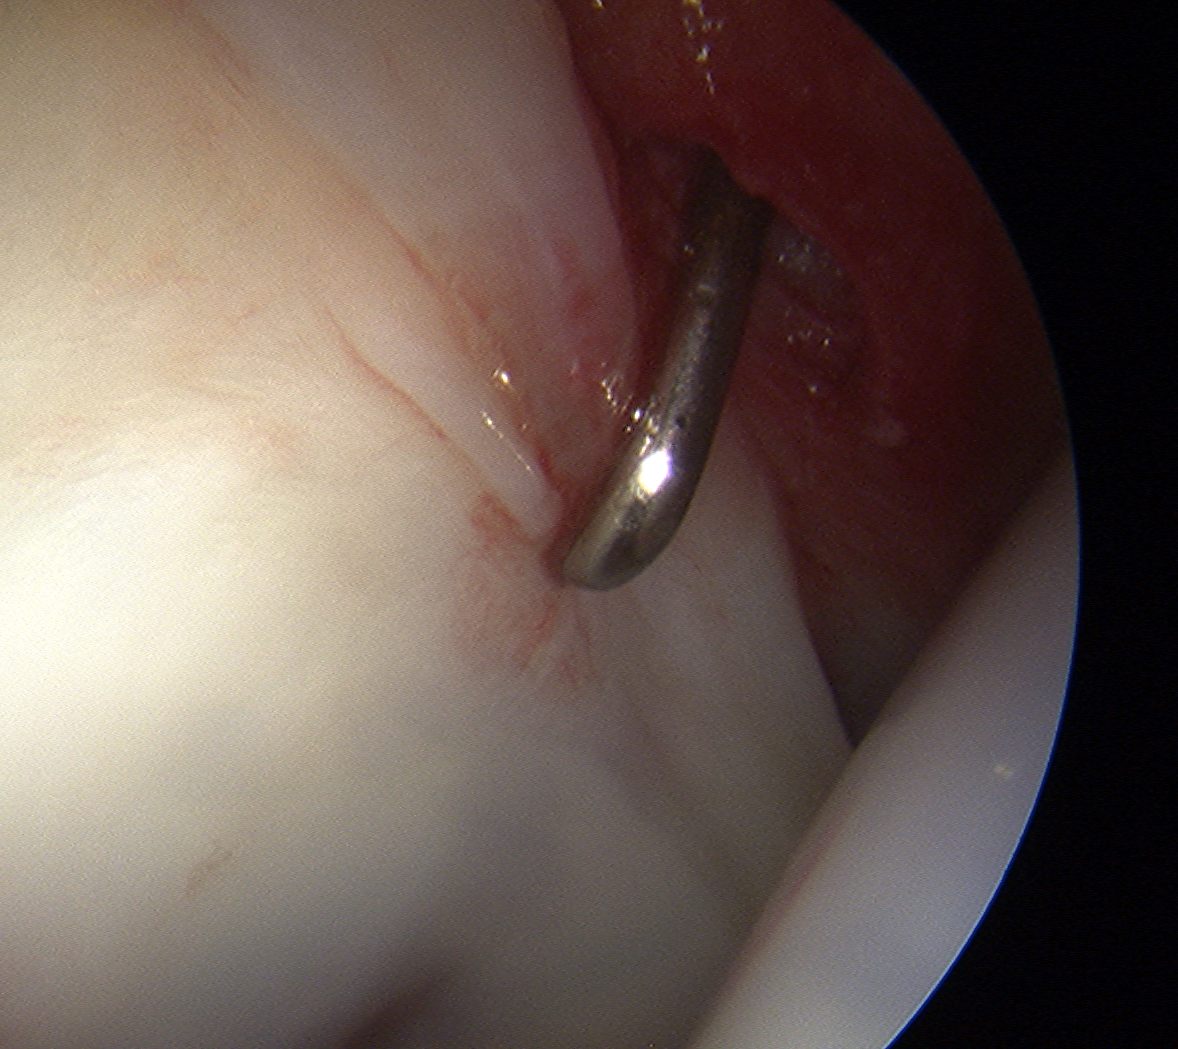

- insert just above head to avoid translabral penetration (between acetabulum and labrum)

PALA

Insertion of PALA under image intensifier